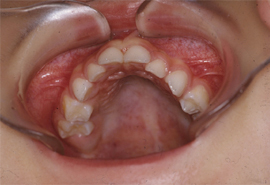

※日本小児歯科学会HPより転載 |

【写真4】 写真3と同一児で、上顎歯列は前突,頬窄してV字形を呈している。 |